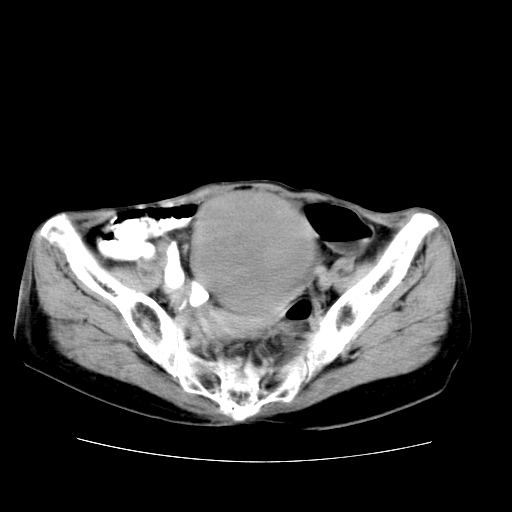

女性,72岁。

主诉下腹部坠痛不适1年余。

子宫增大如孕3月大小,质软,活动可,无压痛。

b超提示:盆腔(子宫前方)低回声团块。

临床诊断:盆腔肿块查。

1、这个肿瘤密度均匀,增强后轻中度均匀性强化,与左侧附件关系密切,肿瘤边缘光整、清晰。

2、左侧卵巢增大呈8×8×10cm大小,实性,表面光滑,边清,左侧输卵管爬行于左卵巢上,子宫萎缩。右输卵管、卵巢萎缩。

3、病理号:092658

左侧卵巢纤维瘤(性索间质肿瘤)

卵巢纤维瘤为良性卵巢性索间质肿瘤,常为单侧发病,当合并腹水或胸腹水时称麦格斯(meigs)综合征,肿瘤切除后胸腹水可消失。ct表现为盆腔内边界清楚的圆形或椭圆形肿块,常有分叶或不规则;肿瘤多为实性,少数为囊性、囊实性,完全囊性者可见壁结节。实性部分与子宫等密度;增强扫描常为轻度强化或几乎不强化。